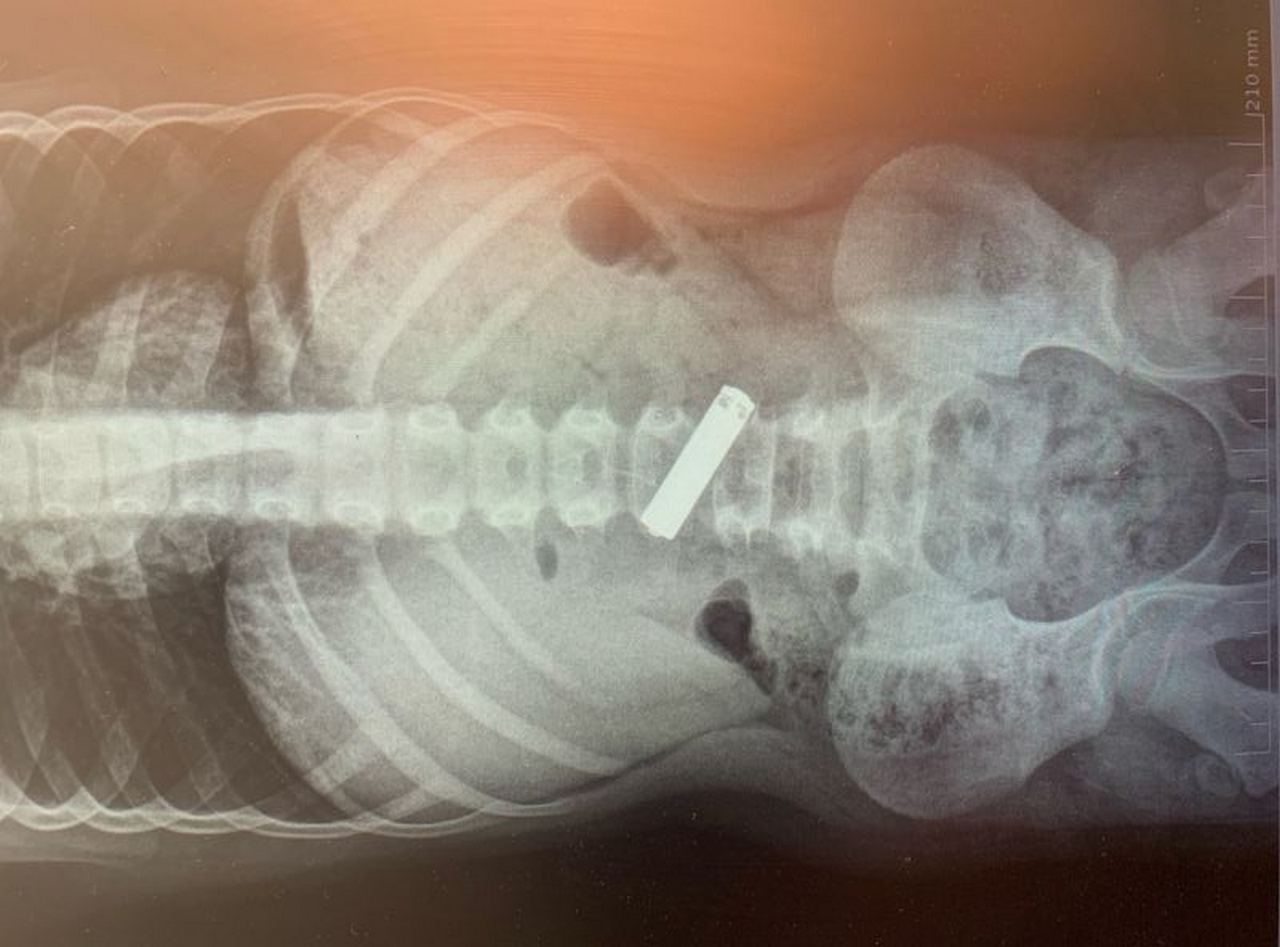

Врачи принялись осматривать юного пациента. Сделали ему рентген органов брюшной полости. И нашли то, что искали: инородное тело в желудочно-кишечном тракте.

Взвесив все факторы: возраст пациента, характер инородного тела и т.п. врачи приняли решение - сделать мальчику общее обезболивание. После чего эндоскопист Александр Климов с помощью минимального количества разрезов и трубки с чёткой оптикой удалил из плоти ребёнка злосчастную батарейку.